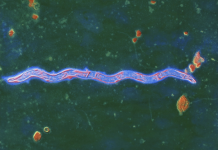

Энцефалит: причины, диагностика, лечение

Почему возникает воспаление головного мозга, чем оно грозит и как его лечить. Энцефалит – это воспаление головного мозга. Самой распространенной причиной развития этого заболевания является...